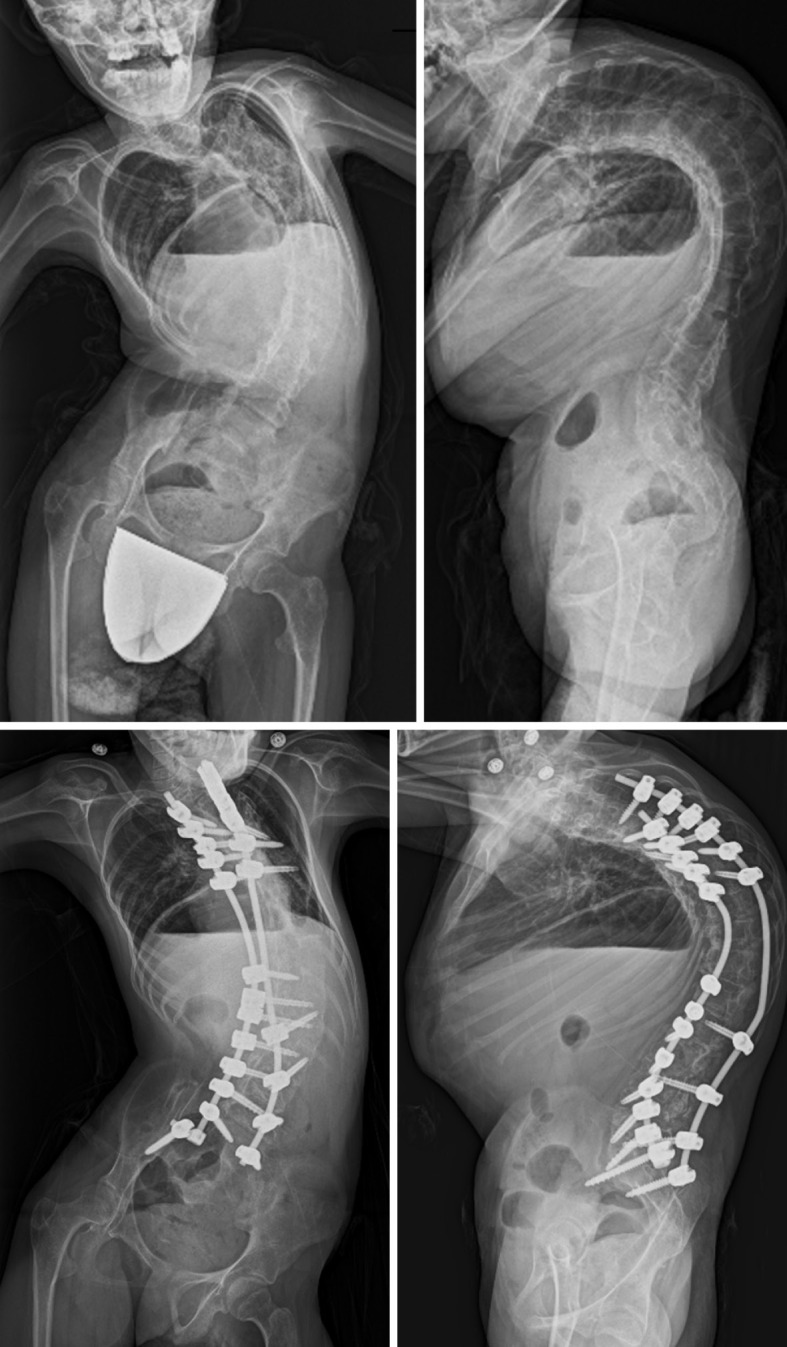

A Case of Early Onset Scoliosis with Trisomy 1q and Monosomy 21q.

Abstract Image